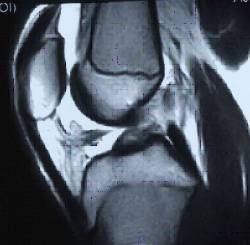

Es importante considerar que la base del diagnóstico es clínico basándonos en la anamnesis y la exploración clínica.

Las exploraciones complementarias pueden no coincidir con el diagnóstico clínico pudiendo llegar hasta un 40% de falsos negativos según las series publicadas.

Los tratamientos convencionales descritos para la reparación del ligamento cruzado anterior pueden provocar efectos yatrógenos sobre el cartílago de crecimiento.

El factor determinante en la posibilidad de la aparición de estos efectos adversos no es la edad cronológica del paciente sino su estadio madurativo (estadios de Tanner <II determinados por la aparición de caracteres sexuales secundarios).

También están involucrados en la posibilidad de lesionar el cartílago de crecimiento el tipo de injerto utilizado (con pastillas óseas) , una excesiva tensión del mismo a la hora de implantarlo y el diámetro de las tunelizaciones empleadas.